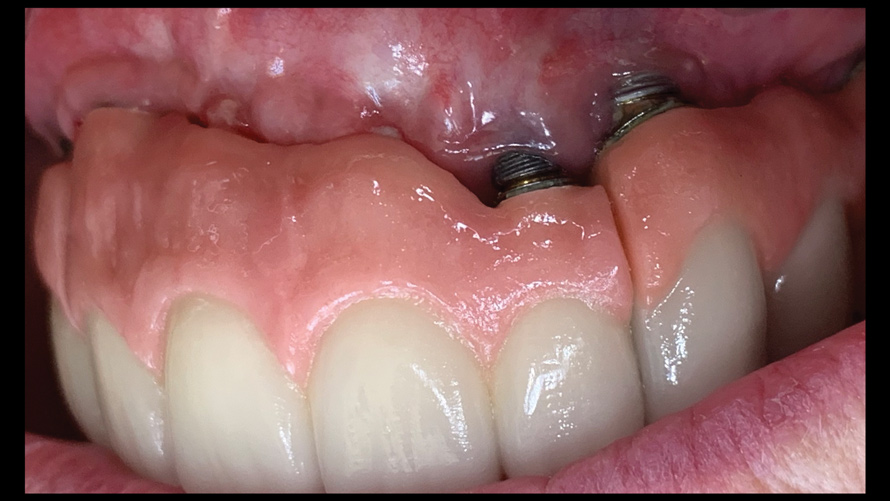

(16. and 17.) Photograph of failing implant prosthetics that may require specialty care taken with a smartphone and an EALS device.

Figure 16

Figure 17